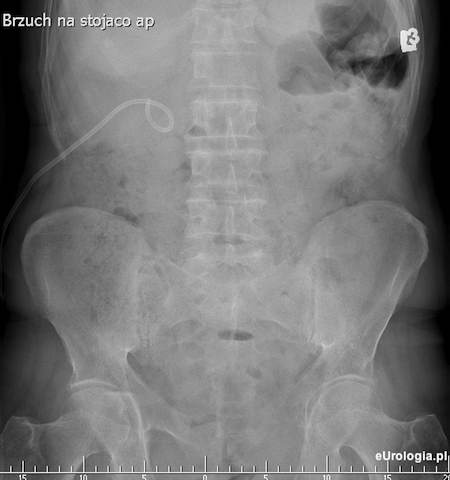

Fot. RTG przeglądowe z widocznym drenem nefrostomijnym założonym do układu kielichowo - miedniczkowego nerki prawej